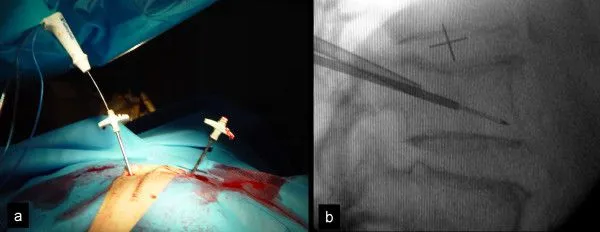

Surgical procedure showing needle insertion with accompanying X-ray guidance.

Step 2: Bore Hole Into Pedicle Bone

A drill is used to bore a hole through the normal pedicle bone of the vertebra.